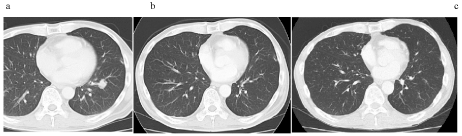

After excluding patients with isolated either para-aortic or left cervical lymph node involvement, those who underwent curative resection of primary gastric cancer and liver metastasis, and those treated with immune checkpoint inhibitors, there were eight long-term survivors of metastatic gastric cancer for more than 5 years after the initiation of chemotherapy in Nagoya Memorial Hospital. The chemotherapeutic responses of eight survivors were CR (n=4), PR (n=1), and SD (n=3); objective response rates (ORRs) was 62.5 % (5/8). Next, there were no long term-survivors with poor PS, i.e., > 3. Figure 1 showed the chronological images of case 1 with recurrent lung metastasis after curative gastrectomy; a single metastatic lesion completely disappeared in response to chemotherapy. Case 2 displayed extensive lymph node involvement and single hepatic metastasis and underwent conversion surgery after chemotherapy, achieving confirmed pathological CR [30]. Case 3 showed severe peritoneal metastasis; therefore, an exploratory laparotomy was performed and palliative chemotherapy was initiated; this patient showed an excellent response to S-1-based chemotherapy and eventually underwent curative surgery 2 years later, yielding pathological CR [30]. Complete disappearance of the primary gastric lesion and multiple liver metastases was revealed in case 4 (Figure 2) [31]. The outcome of our long-term survivors showed that seven cases were free from disease after the cessation of chemotherapy, indicating that palliative chemotherapy can cure metastatic gastric cancer.

Figure 1 Chronological images of case 1.

1. Computed tomography (CT) scans demonstrated a single mass in the lung prior to chemotherapy.

b. Complete disppearance of lung metastasis was observed after 2 cycles of S-1/cisplatin plus paclitaxel.

c. There were no recurrence five years after the cessation of chemotherapy. He then suffered from small cell lung carcinoma, underwent curative surgery, and is still alive